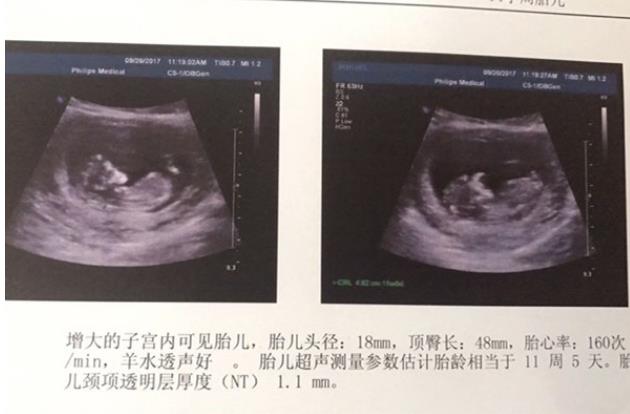

試管會影響胎兒健康么?那些準(zhǔn)備進行試管嬰兒助孕的夫婦經(jīng)常有一個困惑想知道和弄明白:那就是試管助孕降生的孩子和自然懷孕生育的孩子一樣嗎?有什么區(qū)別呢? 試管嬰兒與自然懷孕出生的缺陷是沒有顯著差異的,全球最早出生的試管嬰兒前些年也已結(jié)婚并且生育了自己健康的孩子。研究表明,試管嬰兒與其他自然懷孕的孩子的智商應(yīng)該是沒有差異的,在成長后也不會發(fā)生區(qū)別以及其他的后遺癥。